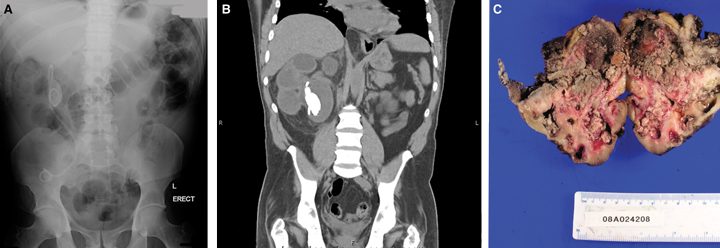

The prospect of a “missed” stent is a constant source of anxiety to the practising urologist. Stents that have been inadvertently left in situ for many months act as niduses for stone formation, particularly at the proximal and distal coils, which may prevent easy stent removal. Encrustation increases stent fragility and may lead to its fragmentation, even during careful attempts at removal. Multiple procedures may be required to remove the stent completely. Encrustation may also impair urine drainage, resulting in unrecognised renal obstruction and silent kidney damage, necessitating nephrectomy. As in our patient, long-term obstruction may cause persistent infection and recurrent episodes of clinical pyelonephritis and subsequent pyonephrosis. From a biological viewpoint, it is not surprising that the combination of stent irritation and infection would lead eventually to malignant transformation,3 although to our knowledge this is the first reported case of ureteric carcinoma associated with a retained ureteric stent.